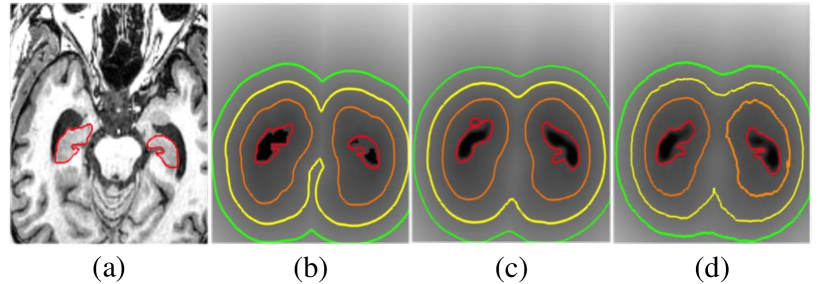

Refer to caption

Figure 4: Qualitative SDM comparison on the hippocampus testing set of (a) axial view input image; (b) groundtruth SDM; (c) predicted SDM with SDM training only; (d) predicted SDM from joint training of SDM and segmentation map. From inside to outside, the red, orange, yellow and green contour represents the 00-, 0.10.10.1-, 0.20.20.2- and 0.30.30.3-distance map, respectively. The grayscale intensity indicates the SDM space. All results are based on the normalized SDM values.

We present a group of axial view SDM plots in Figure 4. One can observe that the learned SDM with only SDM training obtains smoothest contours, while the joint training of SDM and segmentation map predicts more accurate organ boundary. Overall, they both preserve the shape of hippocampus and align well with the groundtruth SDM. Such results prove that predicting SDM directly from the medical image input is feasible and reliable, where shape information is indeed captured during the learning process. Qualitative comparison of segmentation results is illustrated in Figure 5. As aforementioned, segmentation results trained with only segmentation output (blue contours) have false positives due to the lack of shape awareness. According to the results shown in Figure 5 and Table 1, segmentation by jointly training with SDM and binary map supervision get best performances. In conclusion, incorporating segmentation with SDM prediction indeed provides meaningful improvements and generates better single organ segmentation results.